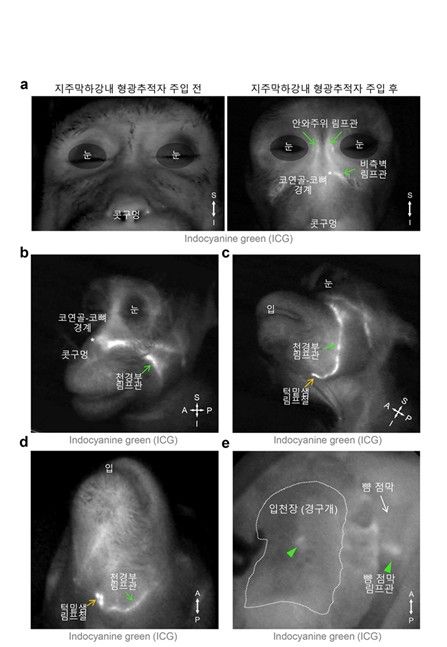

형광물질 이용한 뇌척수액 배출 경로 시각화 형광물질 이용한 뇌척수액 배출 경로 시각화

[IBS 제공. 재판매 및 DB 금지]

연구팀은 생쥐 모델에 형광 표지자를 발현시킨 뒤 생체 내 이미징 기술을 이용해 뇌척수액 배출 경로를 시각화했다. 관찰 결과, 뇌척수액이 눈 주위, 코안 쪽 그리고 입천장 림프관을 통해 눈·코 옆 림프관으로 모인 뒤 턱밑샘 림프절로 배출되는 것으로 나타났다.

연구팀은 한국생명공학연구원 국가영장류센터 이영전 박사 연구팀과 협업을 통해 이런 뇌척수액 배출 경로가 영장류에도 존재함을 확인했다.

영장류에서의 뇌 척수액 배출 경로 영장류에서의 뇌 척수액 배출 경로